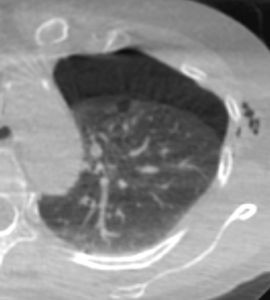

Sono stati inclusi 32 pazienti con 32 noduli polmonari inferiori ai 15 mm sottoposti ad agobiopsia percutanea mediante guida TC a fascio conico con braccio “a C” in un intervallo di 48 mesi da Gennaio 2018 a Dicembre 2021. Le procedure sono state eseguite con ago da biopsia automatico BARD MONOPTY © da 18 G. La biopsia è stata considerata diagnostica in presenza di esito istologico univoco, in assenza di necessità di ulteriori correlazioni anatomo-cliniche e/o in presenza di conferma istologica sul pezzo operatorio e/o con andamento clinico-radiologico al follow-up compatibile con l’istologia. Le complicanze principali della procedura comprendono emoftoe e PNX.

26 biopsie (81.3%) sono risultate diagnostiche. 17 (53.1%) sono risultate positive per malignità e 9 (28.1%) negative per malignità. Delle 6 biopsie non diagnostiche, 5 sono risultate lesioni maligne al follow-up e 1 paziente è stato perso al follow-up. Si sono verificati 18 PNX (56.3%) di cui 2 PNX (6.3%) con necessità di posizionamento di drenaggio toracico e 2 casi di emoftoe (6.3%) risolti con la variazione di decubito.

La TC a fascio conico é un valido supporto per l'agobiopsia percutanea di noduli polmonari di piccole dimensioni. I frustoli prelevati risultano diagnostici in un’ alta percentuale di casi con frequenza comparabile ai dati della letteratura riguardanti biopsie polmonari sotto guida TC spirale o TC a fascio conico. Il tasso di PNX è lievemente più alto che in letteratura, pur trattandosi per la maggiore di PNX di minima entità che richiedono esclusivamente il monitoraggio clinico.